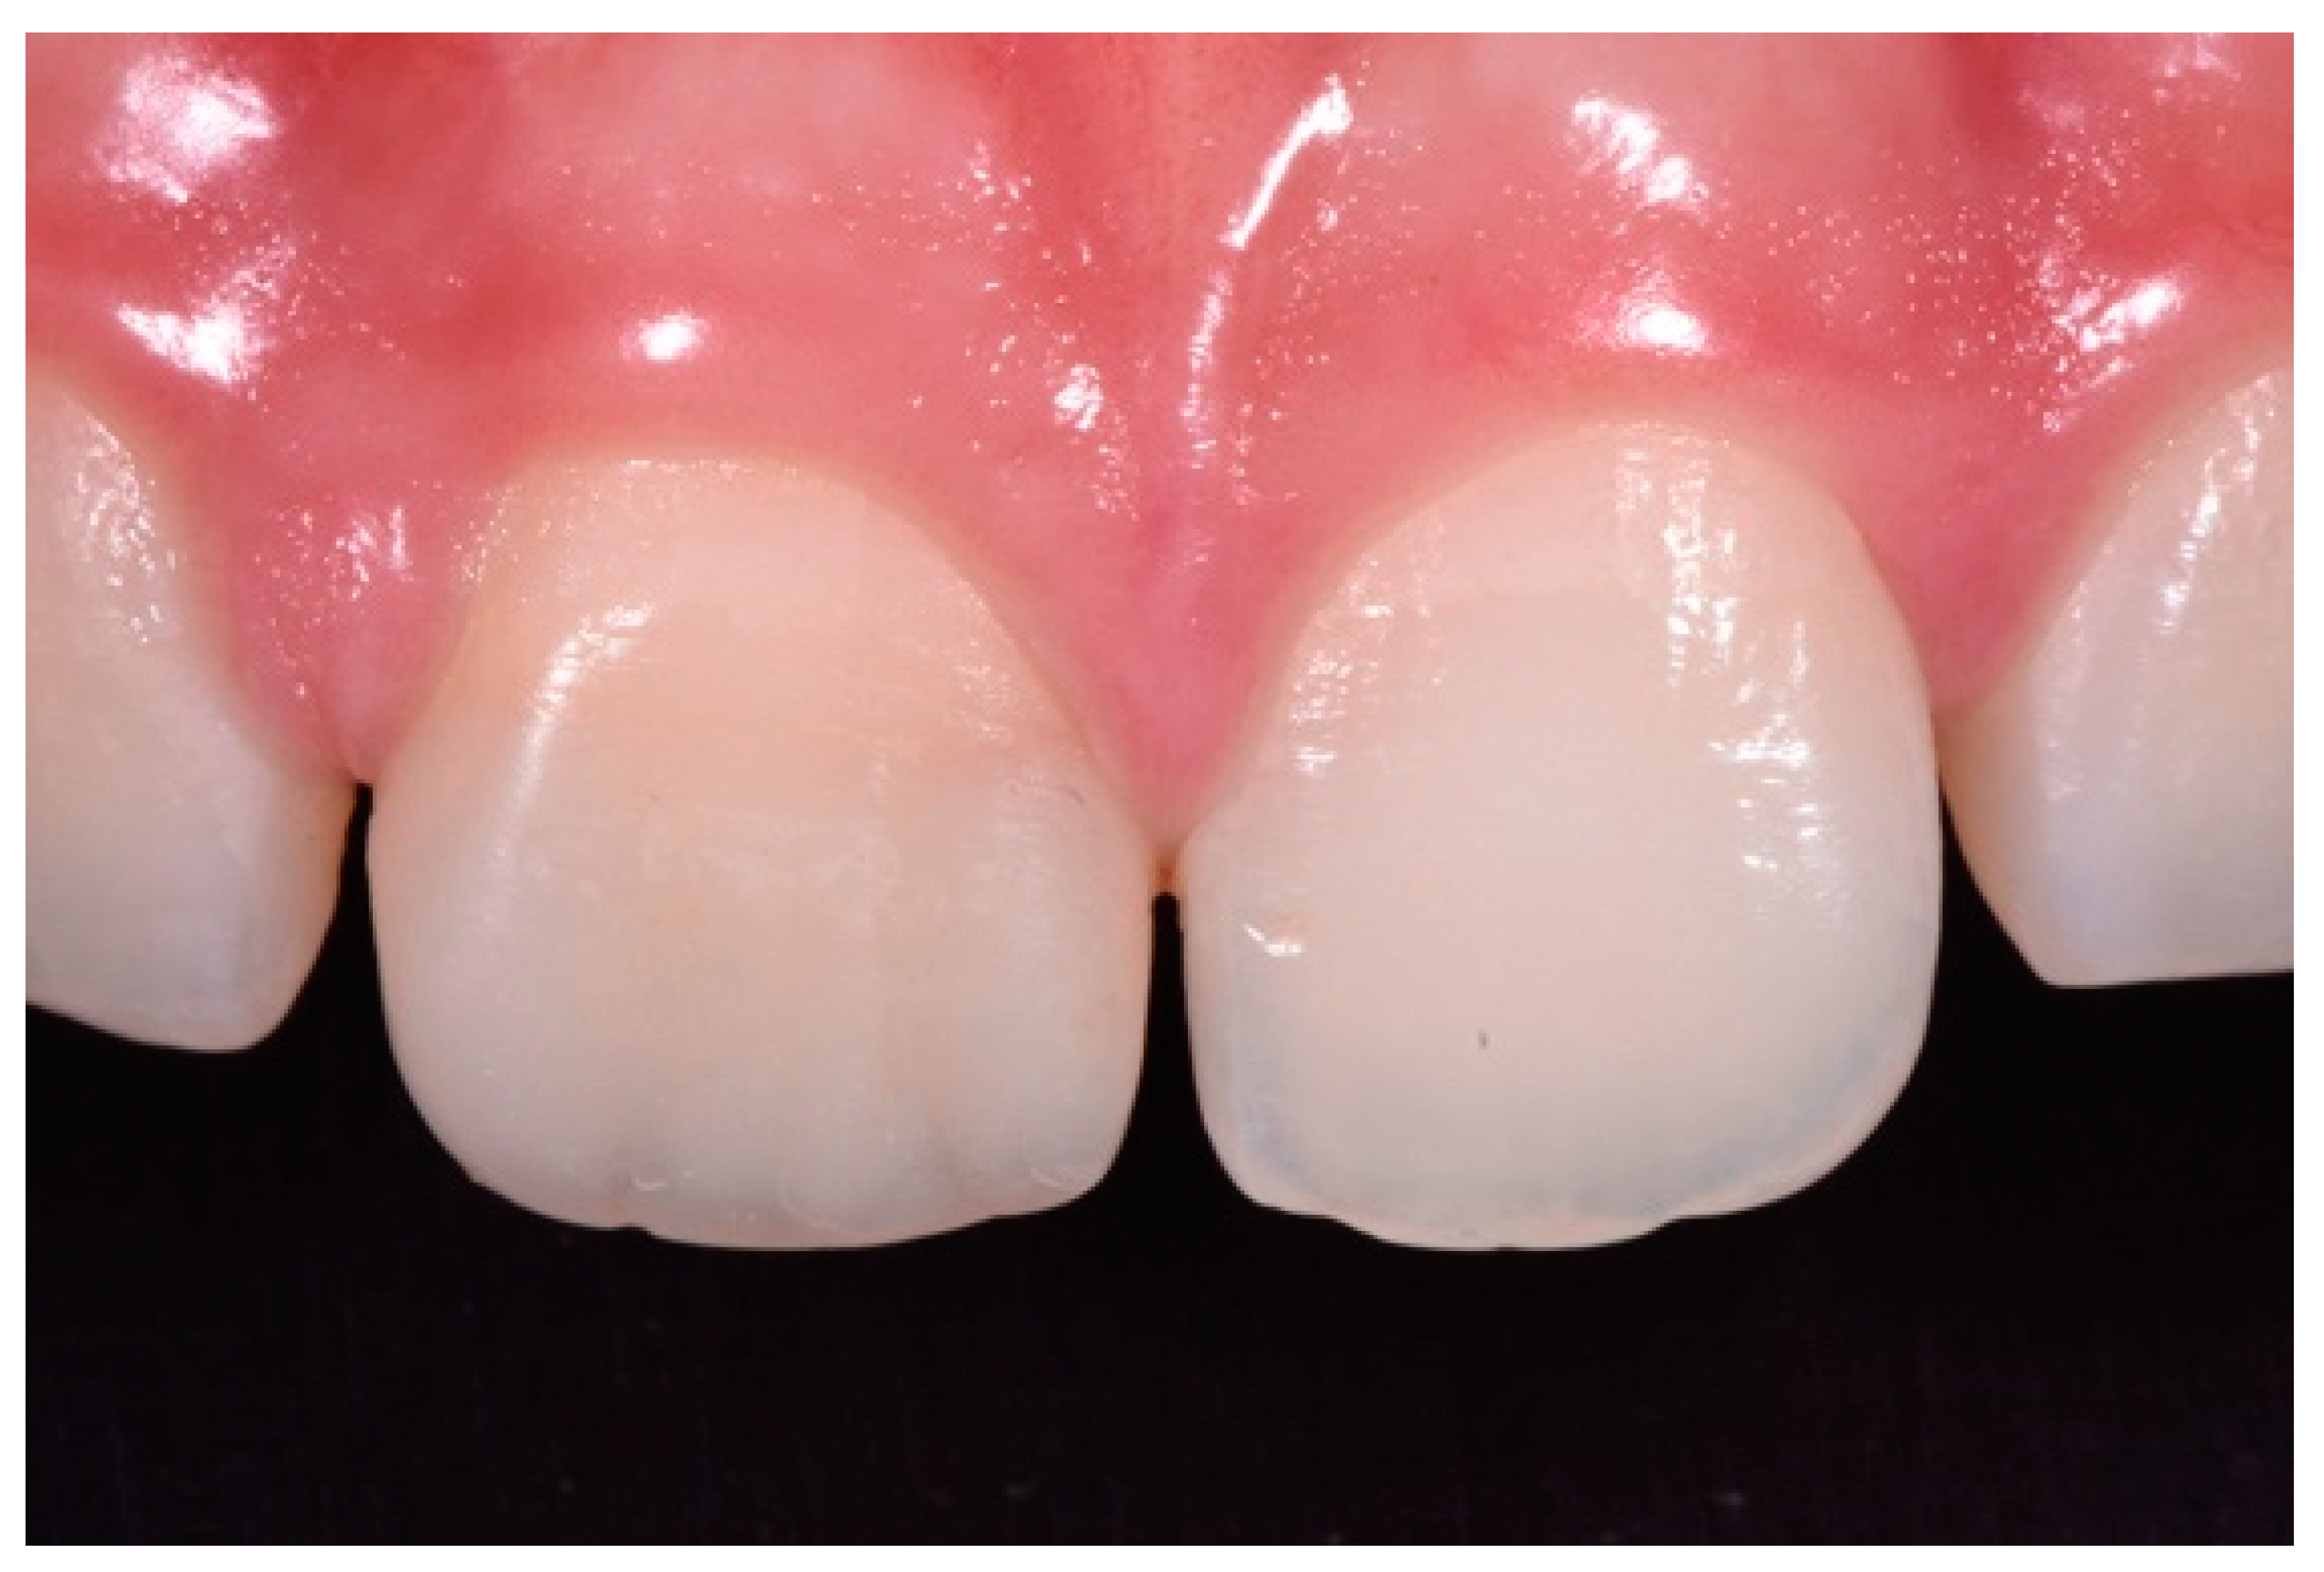

Finishing and polishing procedures were performed with a diamond bur (WL 268 014 Horico, Berlin, Germany), silicone points (Identoflex, Kerr, Bioggio, Switzerland) brushes (Jiffy Goat Air Brushes, Ultradent Products, South Jordan, UT, USA), and diamond pastes (Diamond Polish Mint, Ultradent Products, South Jordan, UT, USA) (Figure 13 and Figure 14). Satisfactory clinical and radiographic outcome was considered satisfactory at 3-months, 1-year, and 5-years post-operative (Figure 15, Figure 16, Figure 17, Figure 18 and Figure 19).

Figure 18.

Five years post-operative.